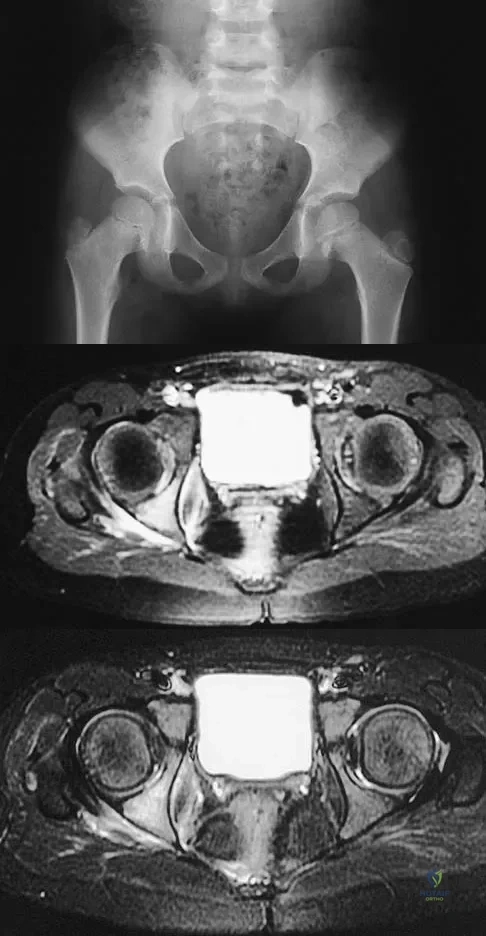

Question 53High Yield

Figures 20a and 20b show the AP and lateral radiographs of a 62-year-old man who has had hip pain for the past 3 weeks. Figure 20c shows a CT scan of the abdomen and pelvis. A needle biopsy specimen is shown in Figure 20d. Preoperative management should include which of the following?

Explanation